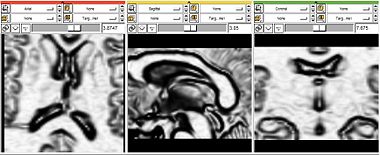

Target1.png

The purpose of this filter is to create a feature image that is suitable for a level-set algorithm, from an intensity image.

It takes the original image and performs anisotropic gaussian diffusion on it, reducing the noise while preserving the edges.

Then the magnitude of the gradient is computed. This magnitude is then non-linearly remapped so as to get very small values in the image edges and very big values in homogeneous areas.

There is only one panel available in this module:

Panel

The parameters have the following meaning: